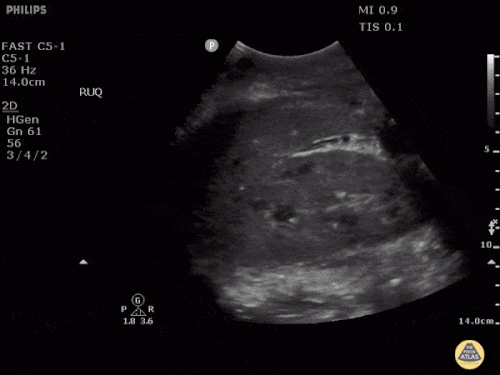

FAST: Morrison Alanı ve Normal FAST Görüntüleri

Normal FAST – Sağ Üst Kadran (RUQ)

Normal FAST – Sol Üst Kadran (LUQ)

Değerlendirmede amaç hipoekoik veya anekoik sıvı saptamaktır. Hipotansif travma hastasında peritoneal boşlukta görülen hipoekoik sıvı genellikle kan olarak kabul edilir.